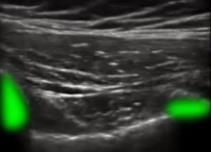

肺部肋骨图像

高亮区域:肋骨